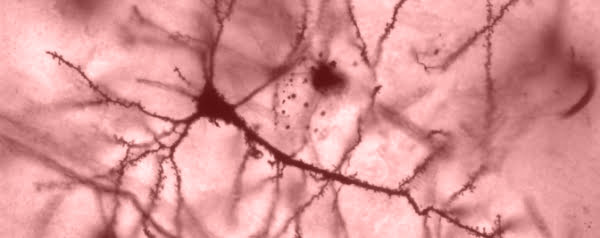

Neuropatische pijn wordt veroorzaakt doordat zenuwen die het stofje GABA (gamma-aminoboterzuur) produceren gedeeltelijk of helemaal niet meer werken. GABA is een neurotransmitter die het doorgeven van signalen in neuronen, en dus ook pijnprikkels, remt. Er zijn medicijnen die GABA-productie verhogen, maar die werken niet in alle gevallen of hebben soms vervelende bijwerkingen als geheugenverlies.

Het team van Allan Basbaum haalde zenuwstamcellen uit de hersenen van muizenfoetussen en zette die over in het ruggenmerg van muizen met beschadigde neuronen. De getransplanteerde cellen vervingen de beschadigde GABA-zenuwen en na vier weken waren de muizen flink opgeknapt.